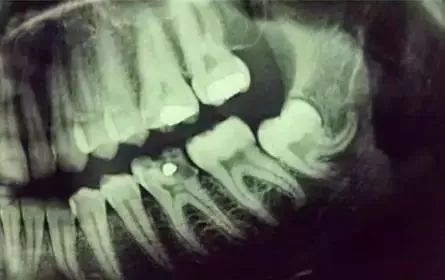

下面这个是接近牙髓了。

牙齿的牙根,是埋在牙槽骨中的。

医生没有透视眼,为了解患牙的牙根的形态、走向、长度及根尖周有无病变及病变大小,或者怀疑有肉眼无法确认的其它牙科问题,都会建议患者去牙科的X光,甚至口腔CT,来全面性地确认问题,以制定合适的治疗计划。